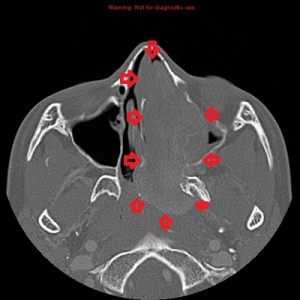

Second panel, left to right: The same set of images as in the first panel, but in bone window, showing bowing of the medial wall of the left maxillary sinus and opacified maxillary sinuses. There is no bone destruction or invasion.

Third panel, left to right: The first 2 images are coronal sections of the face showing the mass-effect of the left nasal mass on other surrounding structure.The third image in this panel is a sagittal paramedian section showing obstruction of the nasopharynx by a soft-tissue mass.